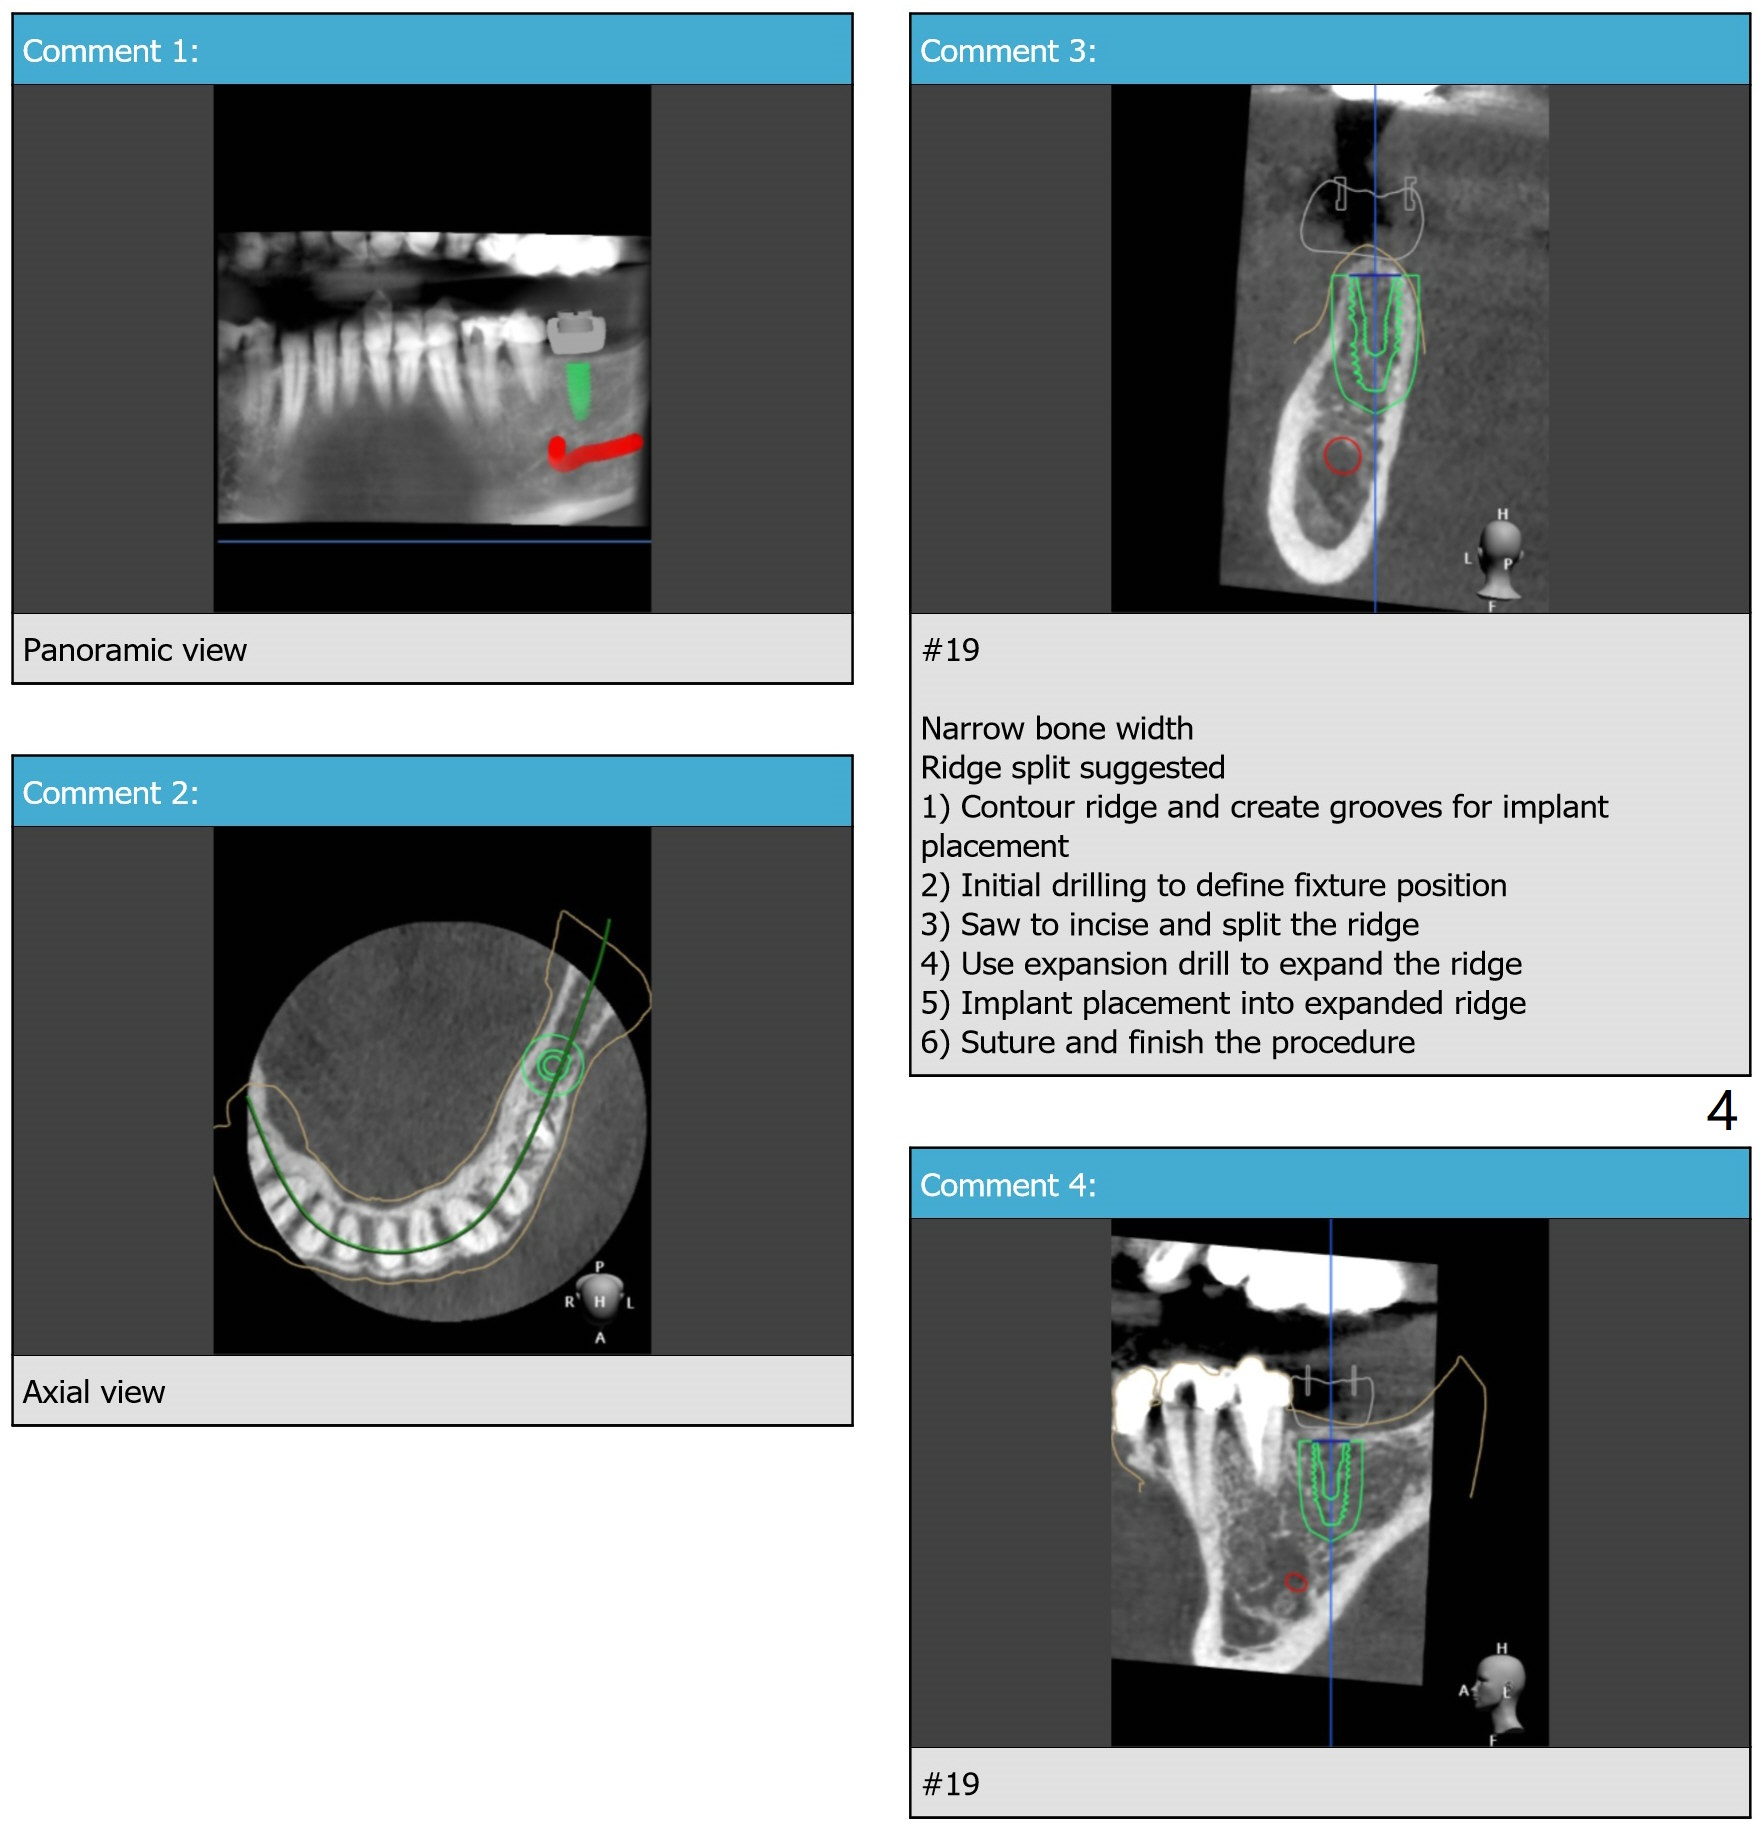

Bone Expansion through Guide

A 53-year-old woman requests implant at #19 after redo #14 crown. The ridge is narrow (holding a 3.5x11.5 mm implant) and apparently low in density (Fig.1). Bone expansion seems necessary. Following use of 2.2 mm drill to the depth, bone expanders will be introduced (1.7/3.1 and 2.4/3.7 mm). After 4.0 mm cortical tap, a 4.0x11.5 mm implant is placed. If torque is high, use 3.5 mm drill. Postop 5x5 cm CT will be taken. Also take pre- and post-op photos of the buccal plate. Prepare surgical handpiece and a new thin fissure bur for ridge split as well as split saw block. Use a UF implant, in consistent with that at #11.